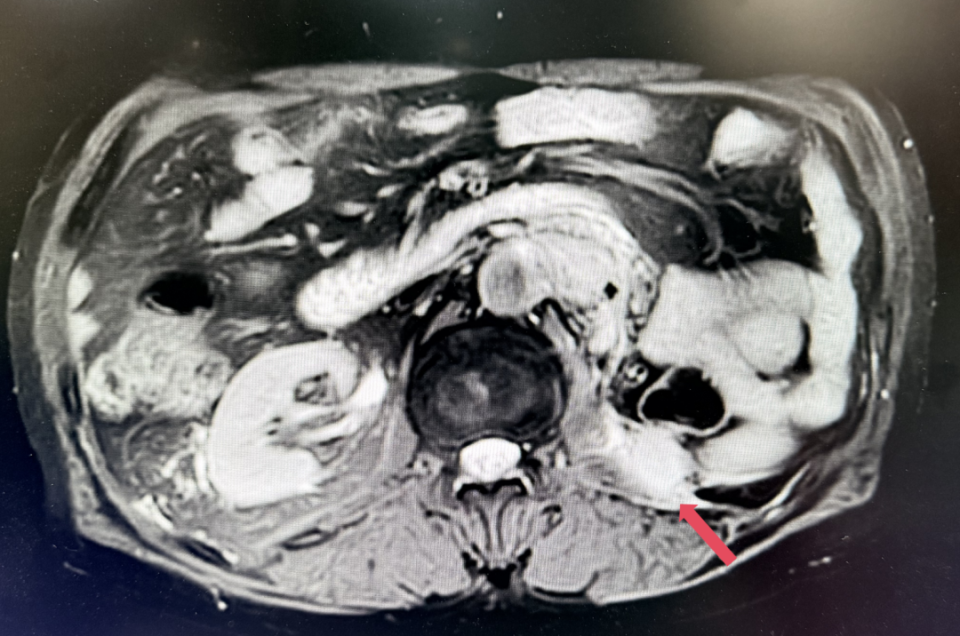

2022年3月:患者因“左腰痛”复查。胸部CT提示双肺微小结节,较前未见明显变化;腹盆MR示:左侧腹膜后多发结节及肿块影,较大者约5.7cm*5.1cm;考虑患者诊断为转移性肾透明细胞癌,IV期,IMDC评分0分,低危组。予培唑帕尼一线治疗8个月,最佳疗效SD。

2023年1月,基线